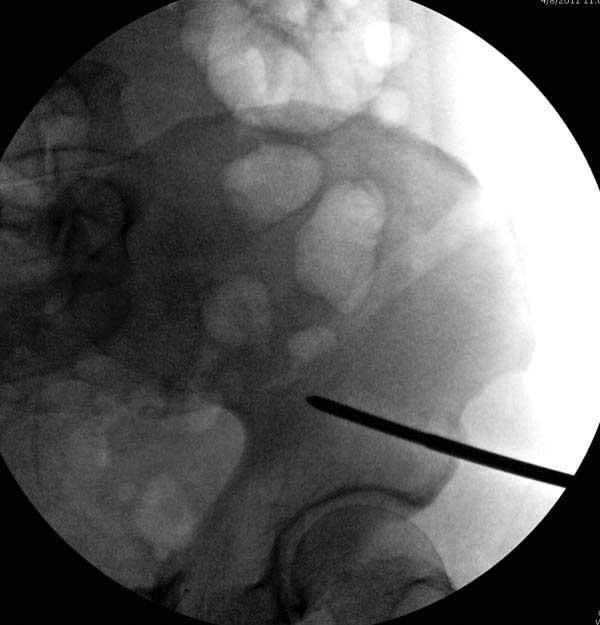

Представлены снимки техники проведения стержней. Через место прикрепления прямой мышцы в Inferior Iliac Spine в направления вырезки создается жесткость. Weber clamp изнутри таза для репозиции, и фиксация после репозиции перелома крыла подвздошной кости. Наружный аппарат удален, нагрузка предполагается через два месяца.